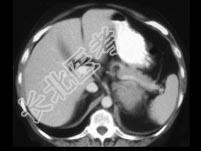

- 单项选择题女,47岁, 满月脸、向心性肥胖伴高血压1月,结合图像, 最可能的诊断是 ( )

A、左肾上腺腺瘤

B、左肾上腺腺癌

C、左肾上腺转移癌

D、左肾上腺嗜铬细胞瘤

E、左肾上腺增生